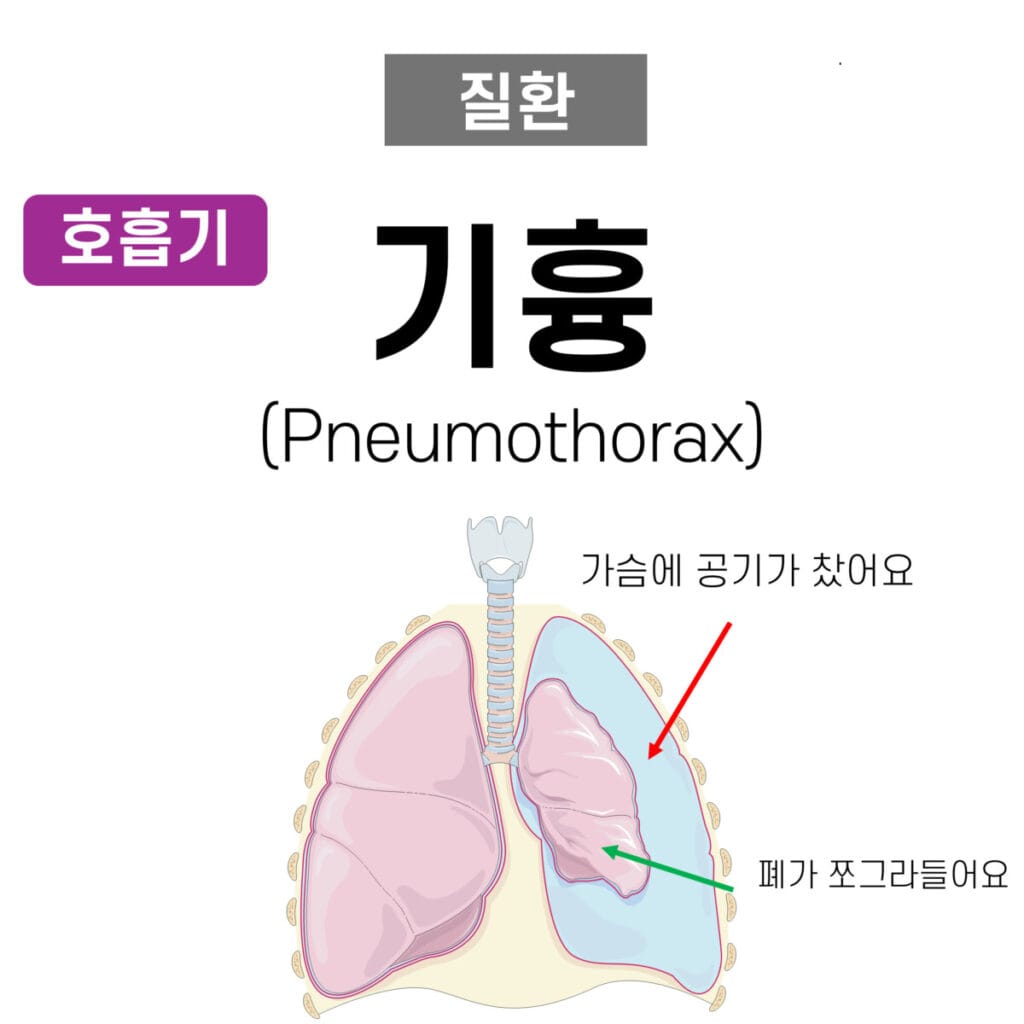

기흉 (Pneumothorax)

| 질환의 정의 |

| 폐와 흉벽 사이의 공간(흉막강)에 공기가 유입되어 폐 허탈을 유발하는 상태. |

기흉(Pneumothorax)는 흉강 내에 공기가 비정상적으로 축적되어 폐 허탈을 유발하는 질환입니다.

✅ 기흉은 원인에 따라 자연 기흉, 외상성 기흉, 긴장성 기흉으로 분류되며, 폐의 부피 감소 및 호흡 부전으로 이어질 수 있습니다.

흉막강 (Pleural Space)란?

- 흉막 (Pleura)은 두겹, Parietal Pleura & Visceral Pleura으로 이루어져있습니다. 흉막강은 그 사이 공간을 말합니다.

임상양상

갑작스러운 흉통과 호흡곤란이 주요 증상으로 나타납니다.

| 주요 증상 |

| ✅ 갑작스러운 일측성 흉통 및 호흡곤란. |

| ✅ 청진 시 감소된 호흡음(affrication sound 감소). |

| ✅ 긴장성 기흉의 경우 저혈압, 청색증, 경정맥 팽창 동반. |